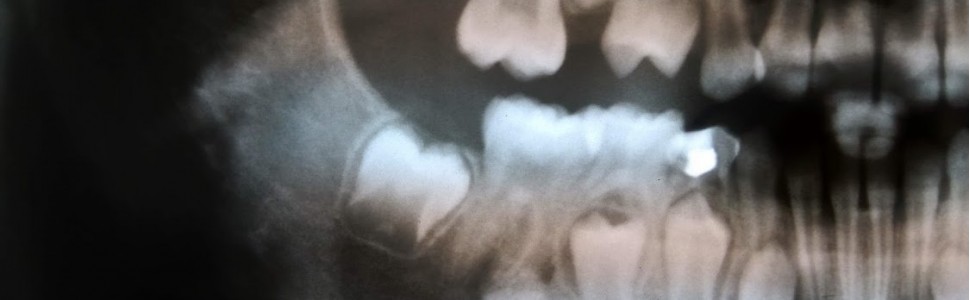

Wyspę kostną opisuje się jak izolowaną, bezobjawową i kontrastującą zmianę występującą w obrębie kości gąbczastej. Przypadek kliniczny 17-letniej pacjentki przedstawia wyspę kostną, obserwowaną po prawej stronie żuchwy na wysokości zębów przedtrzonowych i trzonowych. Z powodu łagodnego charakteru zmiany zalecono okresową kontrolę radiologiczną.

A „dense bone island” is described as an isolated, asymptomatic and radiopaque lesion within cancellous bone. A case report of a seventeen-year patient presents a dense bone island, observed on the right side of mandible in the premolar-molar region. Due to benign character of lesion, the periodical radiological observation was recommended.